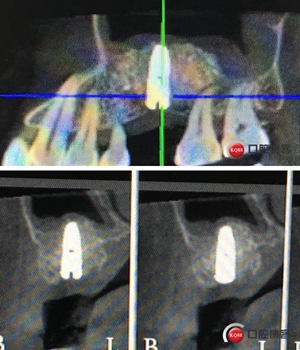

術(shù)后8個月,X光顯示骨量充足,密度明顯增加。

切開翻瓣。

植入一顆4.5x11.5mm長度植體。

植入后X光片。

半年后修復。